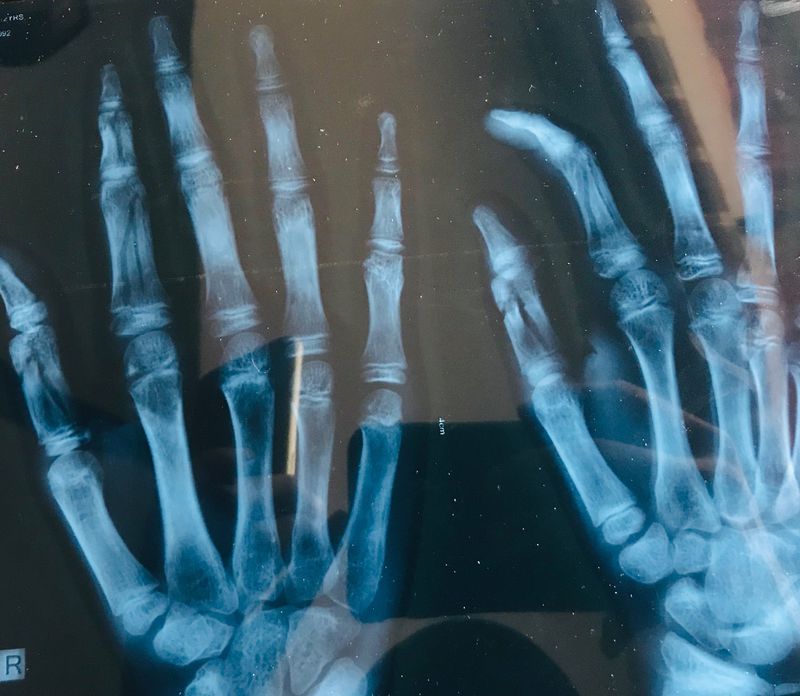

History of falling of concrete slab into the fingers of right hand of a 14 year male boy while moving the slab.

It looks like that kid broke 4 different fingers

Fracture in thumb and index finger??